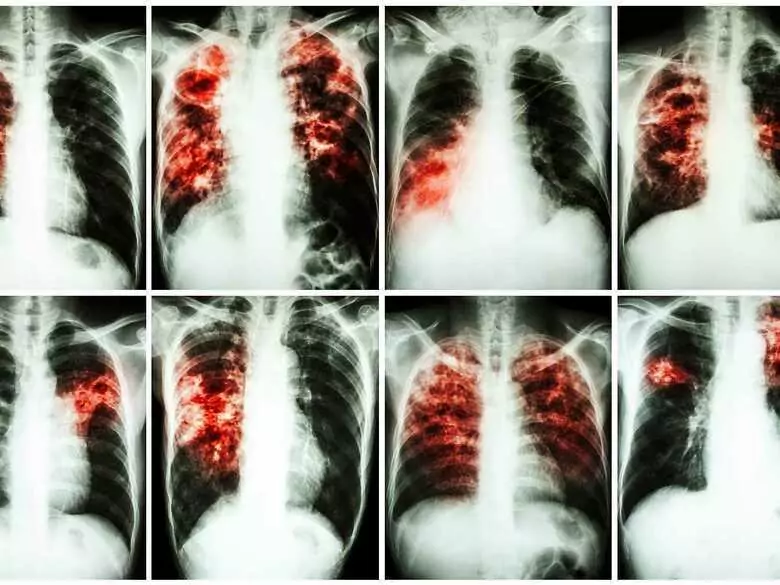

Investigadores de la facultad de medicina de Hradec Králové de la Universidad Carolina de Praga han inventado un nuevo fármaco contra la tuberculosis. El fármaco ha sido vendido a una empresa farmacéutica estadounidense, que desarrollará contractualmente el específico. No obstante, la universidad praguense participará económicamente en los beneficios de la venta del fármaco.